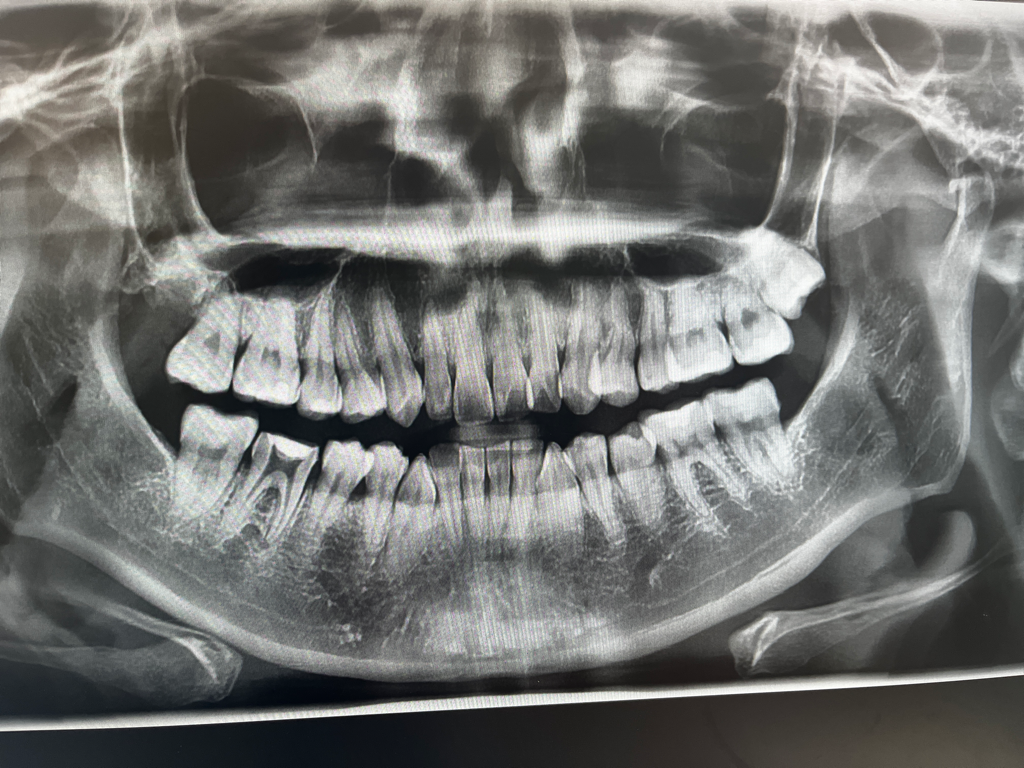

신경치료를 하는치아는 크게 이상이 없어보이고 위쪽 오른쪽 앞니는 엑스레이 상에서 뿌리끝에 염증이 있습니다. 불편하시면 신경치료를 해야될 가능성이 있습니다.

신경치료중인 치아주변의 치조골은 이상이 없이 치료가 잘되고 있는것으로 보입니다

신경치료를 하는 동안에는 해당치아에 힘이 가해지지 않도록 하는것이 중요합니다